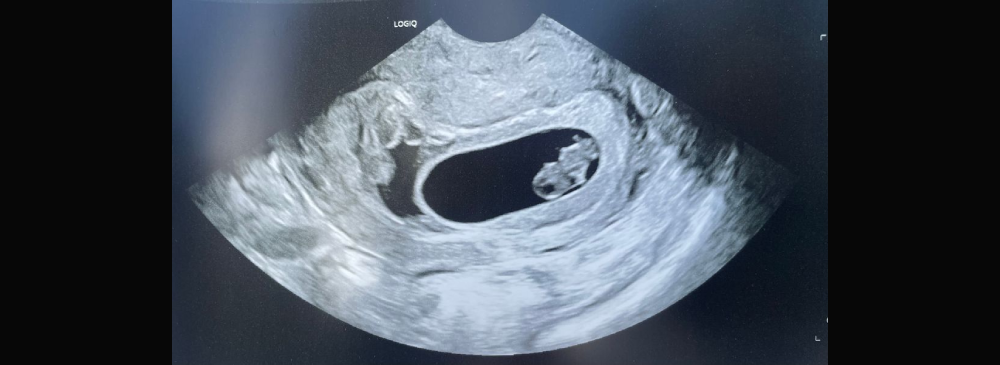

An early Pregnancy/ dating scan is typically performed between 6 to 12 weeks of pregnancy. This non-invasive ultrasound not only confirms your pregnancy but also checks for the fetal heartbeat, gestational age, and the number of embryos. Whether it’s your first child or your third, our experienced radiologists ensure you receive accurate, timely, and detailed information during this important early stage.

An Early Pregnancy/ Dating Scan is the first ultrasound performed during early pregnancy, usually recommended between 6 and 12 weeks. It uses high-frequency sound waves to create images of the developing embryo in the uterus. This scan is crucial for establishing how far along the pregnancy is and helps in predicting the expected date of delivery (EDD). It's also a key way to confirm the baby’s heartbeat and rule out ectopic or multiple pregnancies.

Performed using a transabdominal or transvaginal ultrasound probe, depending on how far along the pregnancy is, the scan provides important insights into fetal development at a very early stage. It's safe, painless, and extremely helpful for women with irregular menstrual cycles, or who are unsure about their last period date.

The experience is simple, quick, and non-invasive. A transabdominal ultrasound is usually done by applying gel over the abdomen and using a probe to capture fetal images. If the baby is too small or unclear on this method, a transvaginal scan may be done, which provides clearer early pregnancy images and is perfectly safe.

The radiologists will check for the gestational sac, yolk sac, and the presence of a heartbeat. You may be asked to arrive with a full bladder, as this can help provide clearer images during the early weeks. The procedure typically takes around 10–20 minutes and results are usually explained immediately or sent to your doctor.